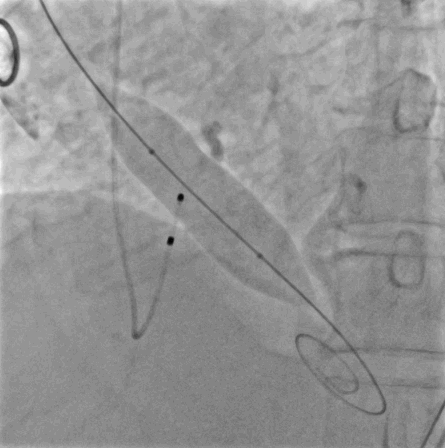

术中精彩影像

主动脉根部造影

球囊预扩

释放到1/2处造影

瓣膜完全、释放形态良好